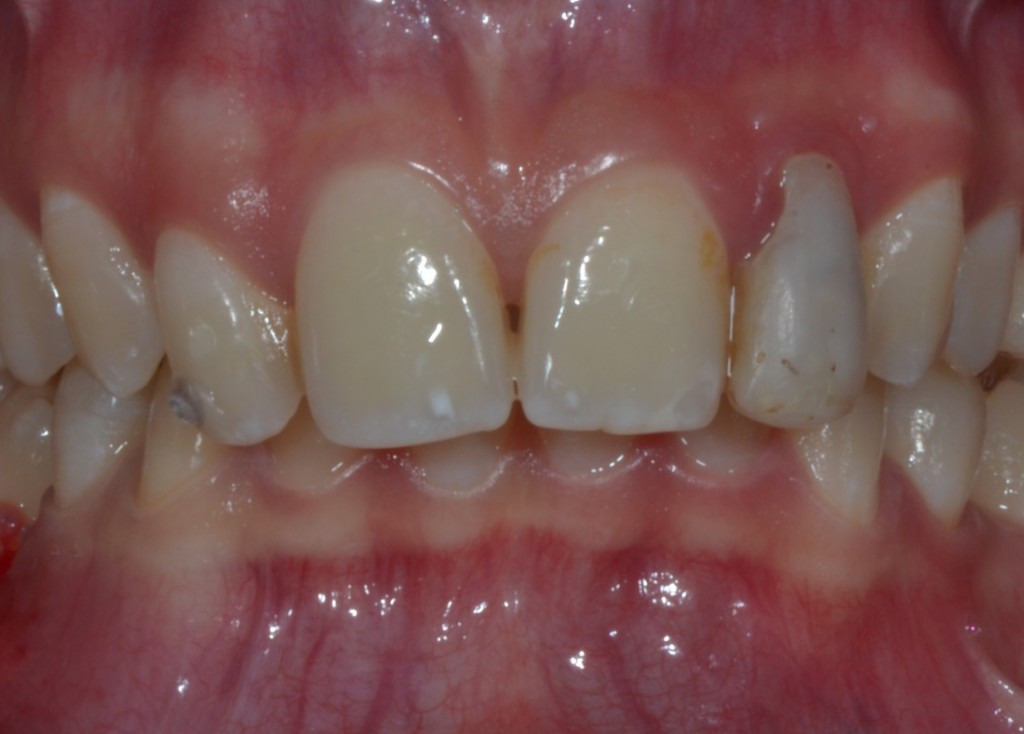

Ora Maddalena, così si chiama la ragazzina di questo dens in dente, con un piccolo allungamento di corona clinica seguito da limatura del margine incisale e una semplice otturazione di 12 e una corona in disilicato preparata su questo dens in dente, può tornare a sorridere. Ecco la foto e la rx a sei mesi dal caso finito. Tutto perfetto! Il 22 sta guarendo e le gengive e i denti stanno alla grande! Il brillantino invece ha perso il diamantino! ?